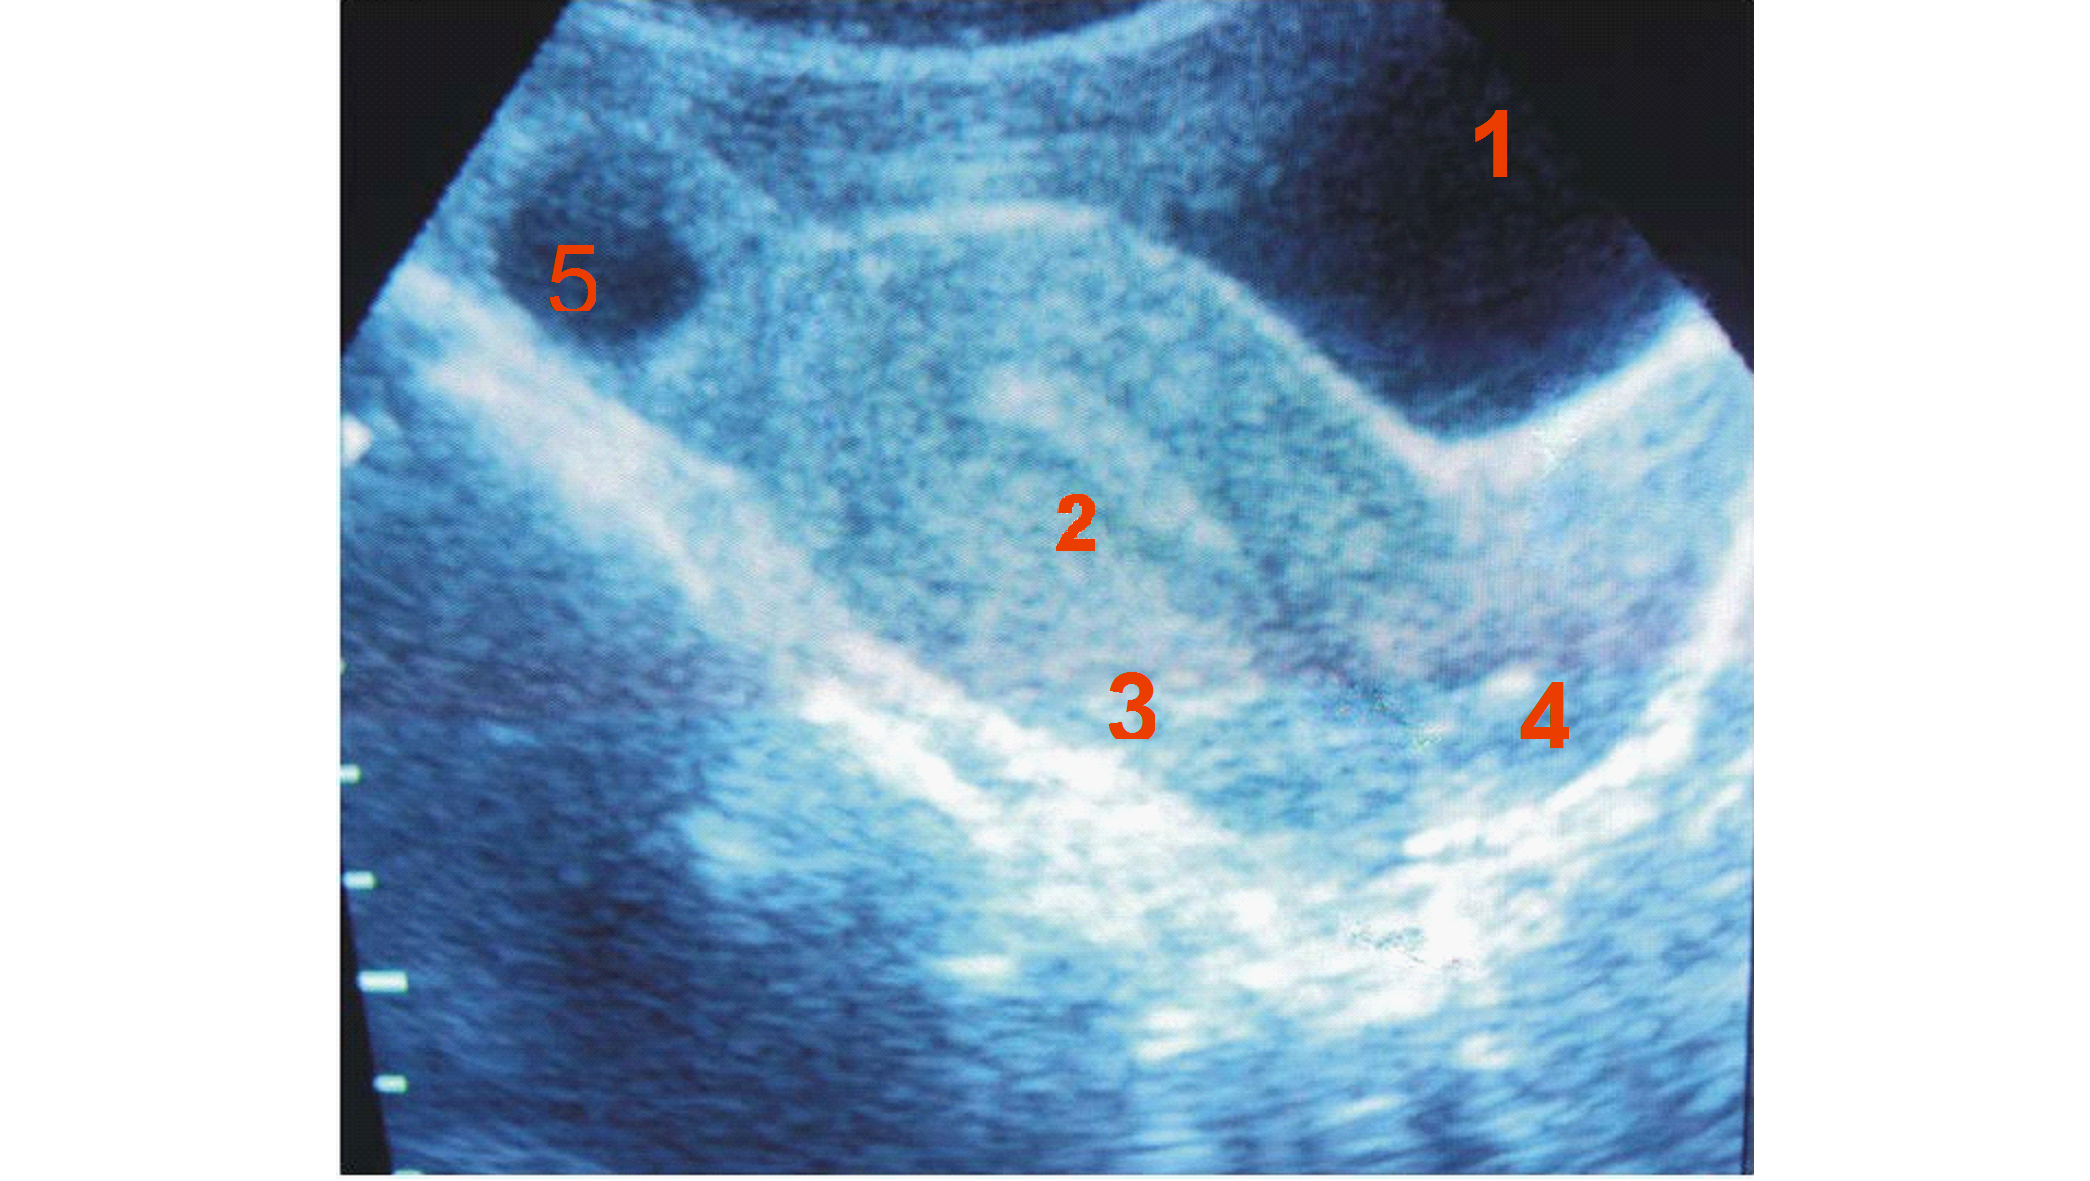

Figure 2a: Showing longitudinal ultrasound scan of the uterus.

Legend

1. Bladder

2. Endometrium

3. Myometrium

4. Cervix

5. Ovarian Follicle